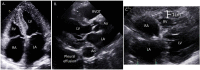

Cardiac amyloidosis (CA) is an infiltrative cardiomyopathy resulting from deposition of misfolded immunoglobulin light chains (AL-CA) or transthyretin (ATTR-CA) proteins in the myocardium. Survival varies between the different subtypes of amyloidosis and degree of cardiac involvement, but accurate diagnosis is essential to ensure initiation of therapeutic interventions that may slow or potentially prevent morbidity and mortality in these patients. As there are now effective treatment options for CA, identifying underlying disease pathogenesis is crucial and can be guided by multimodality imaging techniques such as echocardiography, magnetic resonance imaging, and nuclear scanning modalities. However, as use of cardiac imaging is becoming more widespread, understanding optimal applications and potential shortcomings is increasingly important. Additionally, certain imaging modalities can provide prognostic information and may affect treatment planning. In patients whom imaging remains non-diagnostic, tissue biopsy, specifically endomyocardial biopsy, continues to play an essential role and can facilitate accurate and timely diagnosis such that appropriate treatment can be started. In this review, we examine the multimodality imaging approach to the diagnosis of CA with particular emphasis on the prognostic utility and limitations of each imaging modality. We also discuss how imaging can guide the decision to pursue tissue biopsy for timely diagnosis of CA.